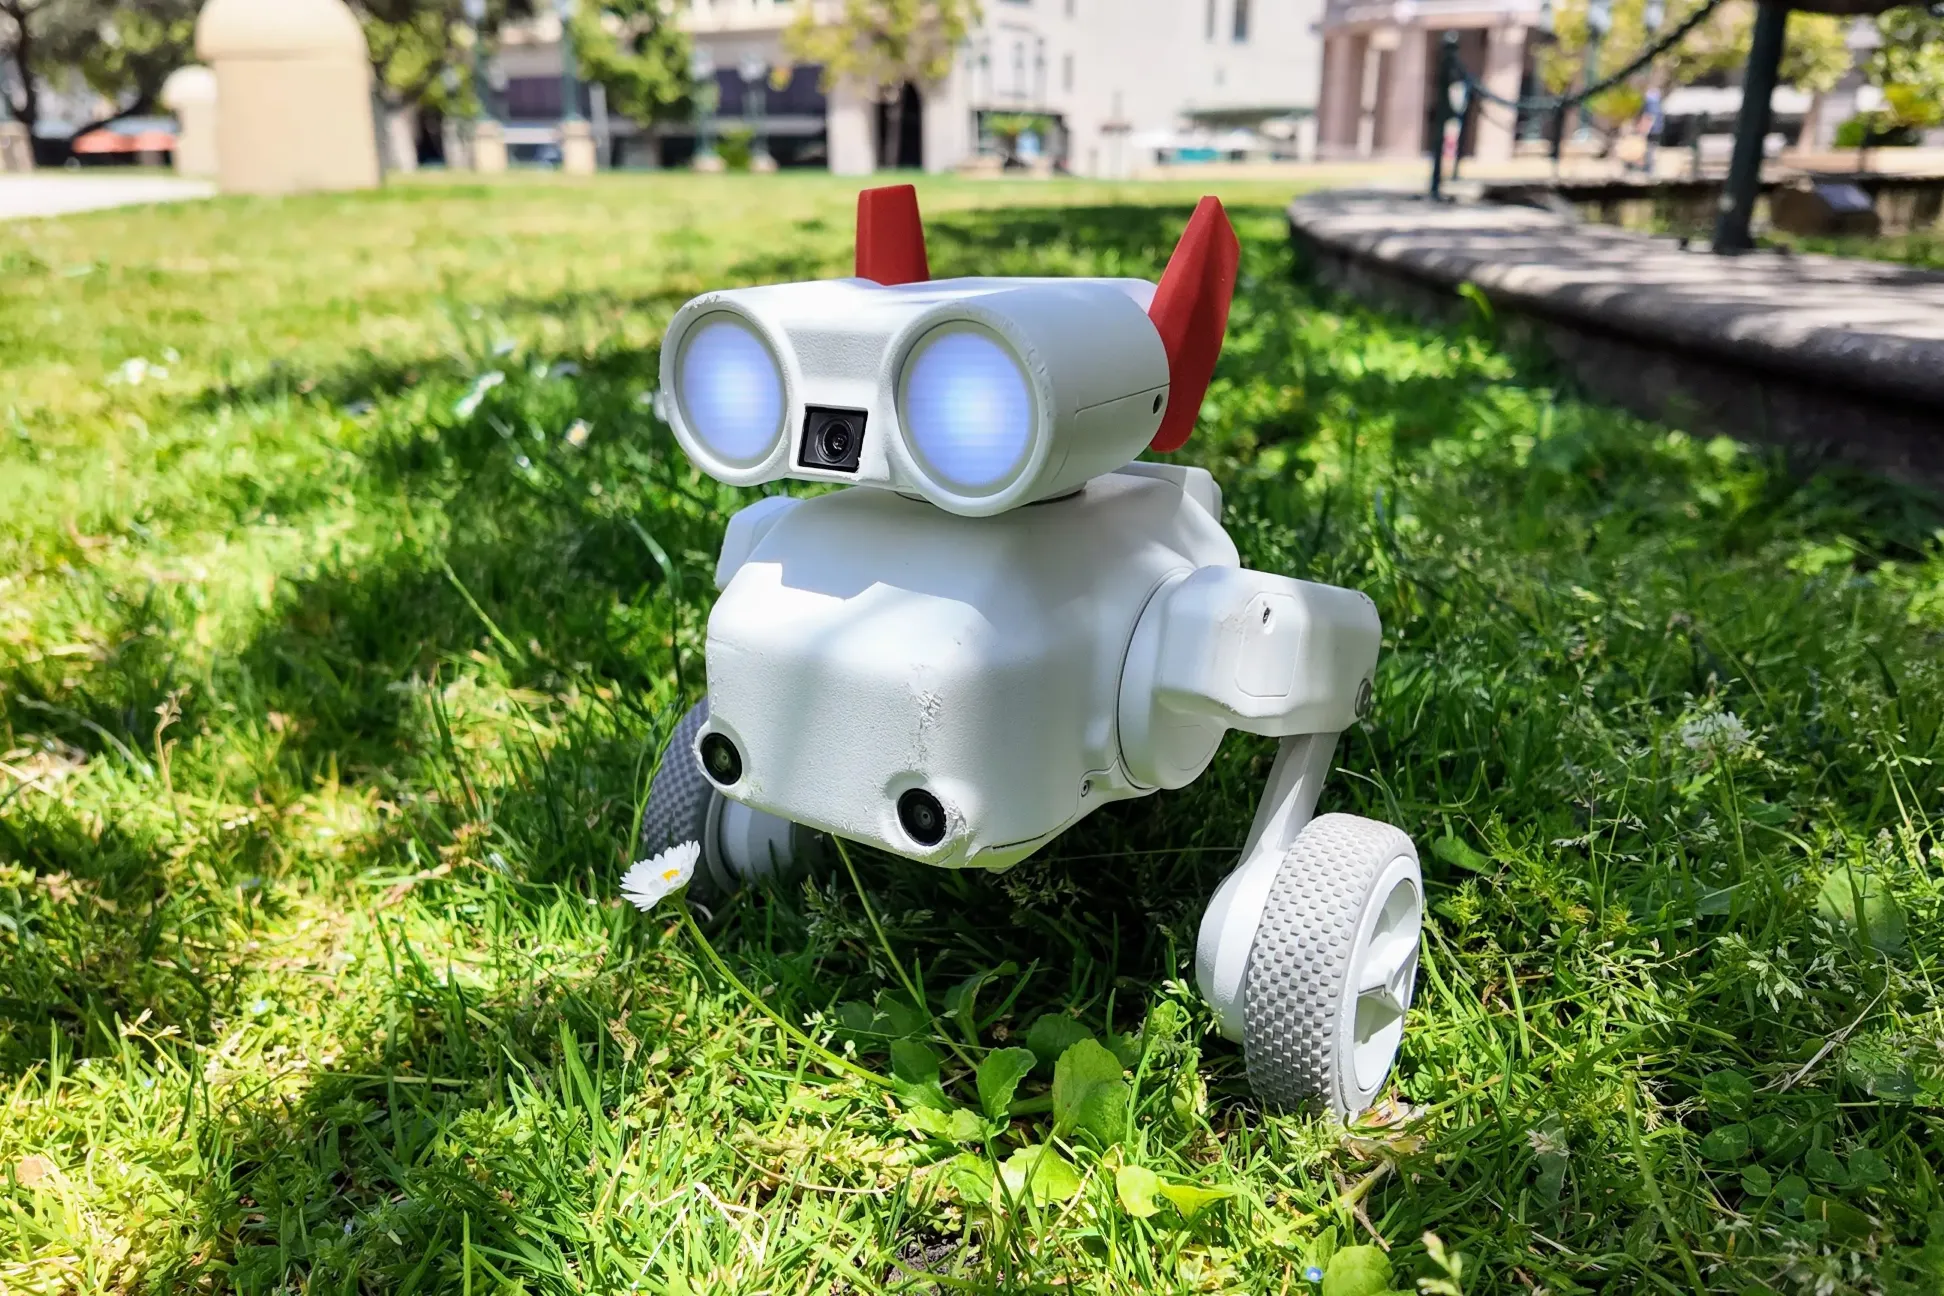

قدیمیترین دستگاهها، «SQUID»ها بودند که نیاز به سرمای شدید داشتند، مثل یخچالهای آزمایشگاهی غولپیکر. اما دکتر طهرانچی و همکارانش، با Pump-Probe، پمپ نوری برای برانگیختن «اتمهای قیصر» (گازی با خواص مغناطیسی جادویی) و حساسیت را ۱۰۰۰ برابر افزایش دادند، آن هم در دمای اتاق.

به مانند گوشی هوشمندی که ضربان قلب را چک میکند، اما هزاران برابر دقیقتر. این پیشرفت، تشخیص ایسکمی را از حدس به علم تبدیل کرد، جایی که ECG معمولی ناتوان است.

مگنتومترهای Pump-Probe، بیمار را بدون تماس زیر خود میگیرند و نقشه سهبعدی میکشند. پژوهش در ۲۰۲۲ دکتر طهرانچی روی بیماران واقعی، دقت ۹۵٪ در مراحل اولیه را نشان داد؛ زودتر از آنژیوگرافی پرخطر.

چگونگی کارکرد سنسورهای جادویی

ساخت این سنسورها، مثل ساخت رادیویی در میان طوفان نویز بود. میدانهای محیطی (از برق خانه تا زمین) مزاحماند. دکتر طهرانچی، با محفظههای «Mu-metal» (فلزی که مغناطیس را بلعیده و بیرون نمیدهد) و فیلترهای نرمافزاری، نویز را صفر کرد. اتمهای قیصر، مثل جاسوسانی حساس، به کوچکترین تغییر واکنش نشان میدهند.